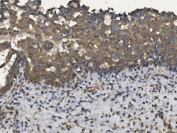

IHC analysis of FFPE human hepatocarcinoma tissue stained with the GCN2 antibody

IHC (Paraffin) : 1:50-1:100